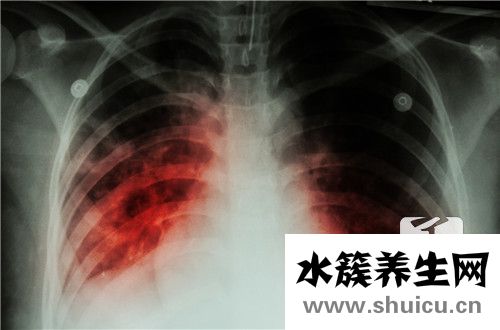

新型冠狀病毒性肺炎是一種嚴重的人肺疾病。 當您患有新的冠狀病毒時,它將主要表現為人的發燒。 另外,很容易引起人體四肢無力和呼吸不良。 它也很容易治療心臟會導致一定損害,并且尚無可治療的新型...